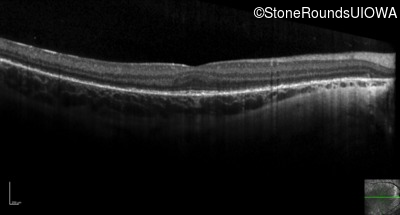

Optical Coherence Tomography - Left - 10/16 sc

Exemplar / OCT Stack

OCT Stack